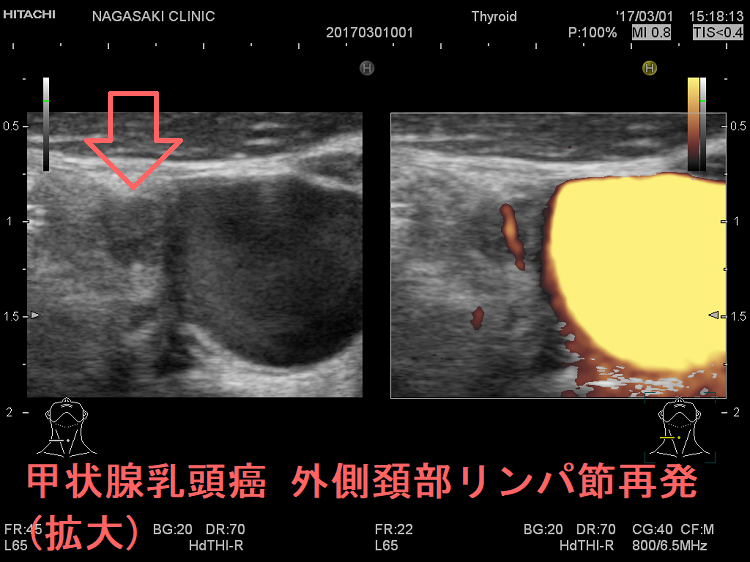

甲状腺乳頭癌 外側頚部リンパ節再発 超音波(エコー)画像

甲状腺乳頭癌 外側頚部リンパ節再発 超音波(エコー)画像 (拡大)

甲状腺乳頭癌 外側頚部リンパ節再発 超音波ドプラー画像 (拡大)